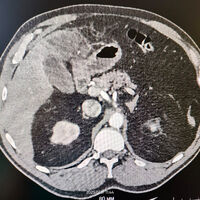

Проглоченная рыбья кость пробила кишечник мужчине и застряла в печени

На Кубани спасли мужчину с застрявшей в печени рыбьей костью

Медики Кущевской центральной районной больницы спасли пациента с рыбьей костью в печени, мужчина три недели не обращался к врачам и занимался самолечением. Об этом в Telegram-канале сообщил министр здравоохранения Краснодарского края Евгений Филиппов.

Мужчина оказался на операционном столе из-за случайно проглоченной рыбьей кости, три недели он испытывал недомогание, но занимался самолечением. Когда состояние ухудшилось, кубанец обратился за медицинской помощью.

В ходе обследования медики обнаружили, что рыбья кость успела пробить кишечник и застряла в тканях печени. Было принято решение о проведении хирургического вмешательства. Операция прошла успешно, инородное тело удалось извлечь. Спустя трое суток мужчина был выписан на амбулаторное лечение.